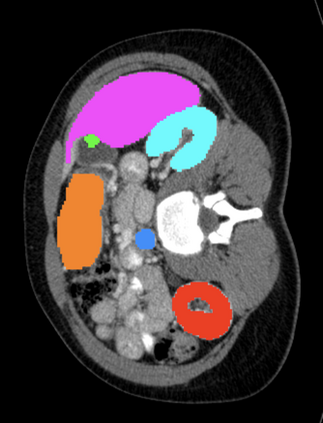

Most recent semantic segmentation methods adopt a U-Net framework with an encoder-decoder architecture. It is still challenging for U-Net with a simple skip connection scheme to model the global multi-scale context: 1) Not each skip connection setting is effective due to the issue of incompatible feature sets of encoder and decoder stage, even some skip connection negatively influence the segmentation performance; 2) The original U-Net is worse than the one without any skip connection on some datasets. Based on our findings, we propose a new segmentation framework, named UCTransNet (with a proposed CTrans module in U-Net), from the channel perspective with attention mechanism. Specifically, the CTrans module is an alternate of the U-Net skip connections, which consists of a sub-module to conduct the multi-scale Channel Cross fusion with Transformer (named CCT) and a sub-module Channel-wise Cross-Attention (named CCA) to guide the fused multi-scale channel-wise information to effectively connect to the decoder features for eliminating the ambiguity. Hence, the proposed connection consisting of the CCT and CCA is able to replace the original skip connection to solve the semantic gaps for an accurate automatic medical image segmentation. The experimental results suggest that our UCTransNet produces more precise segmentation performance and achieves consistent improvements over the state-of-the-art for semantic segmentation across different datasets and conventional architectures involving transformer or U-shaped framework. Code: https://github.com/McGregorWwww/UCTransNet.